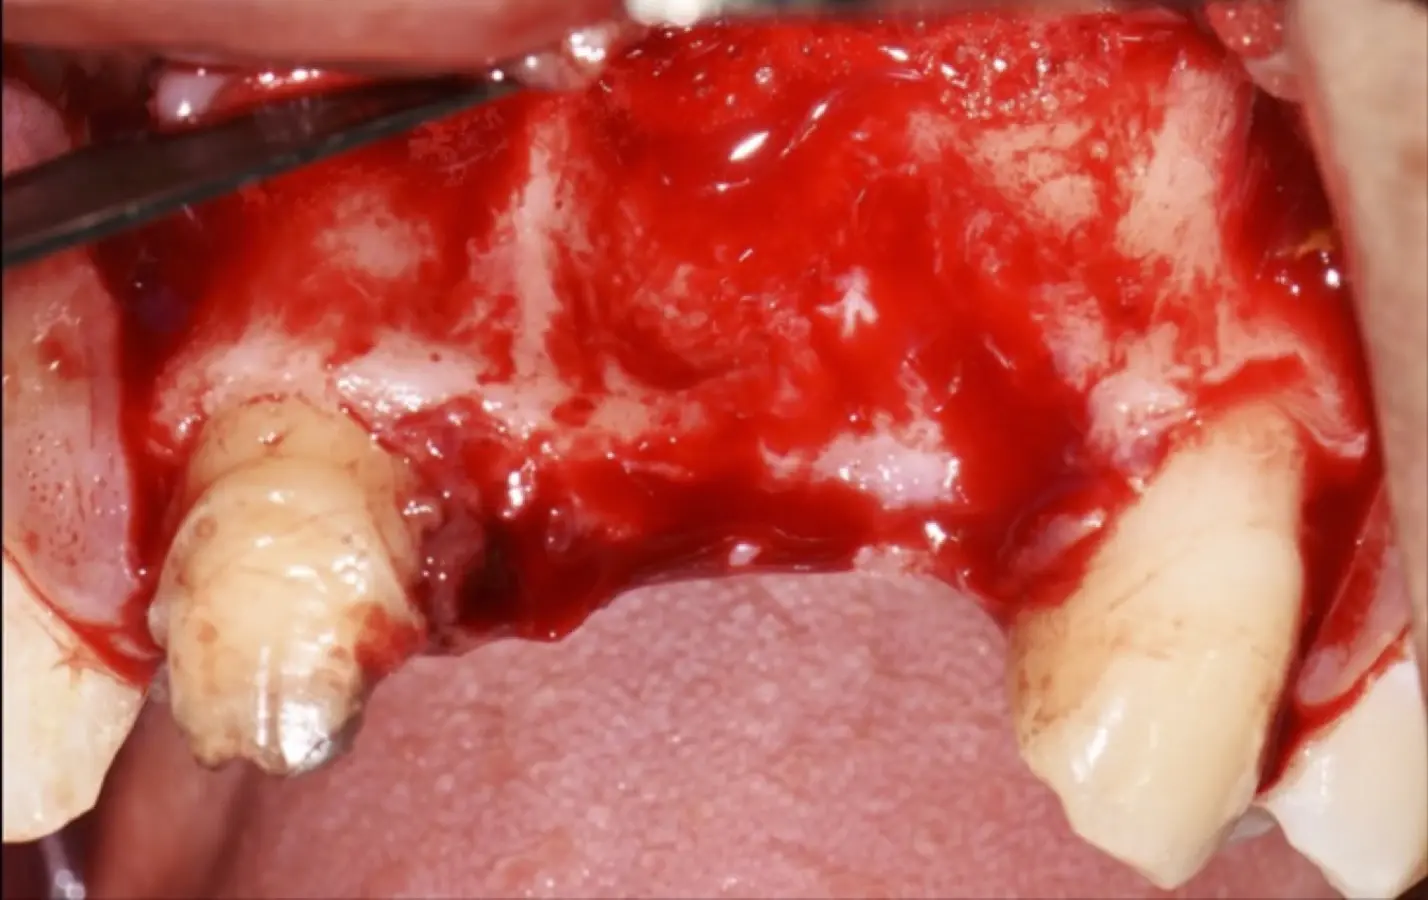

Paciente de sexo femenino de 36 años de edad, llega a la consulta por presentar una restauración protésica inadecuada. En el examen clínico se observa una restauración protésica provisional acrílica sobre las piezas 1.1 y 2.2. Adicionalmente, se aprecia recesión gingival a nivel de la pieza 2.2 y deficiencia horizontal severa de reborde a nivel de la zona edéntula correspondiente a la pieza 2.1. En la evaluación tomográfica se observa ausencia total de tabla ósea vestibular en la pieza 2.2, y se corrobora el déficit en la zona edéntula de la pieza 2.1, para lo cual se indica una reconstrucción de estructuras óseas con hueso en bloque de origen bovino y posteriormente la colocación de implantes dentales.

Figura 35. Decolado a espesor total sobrepasando la línea mucogingival (a, b).

Figura 36. Defecto óseo y severa reabsorción ósea horizontal: vista clínica (a) y corte tomográfico (b).